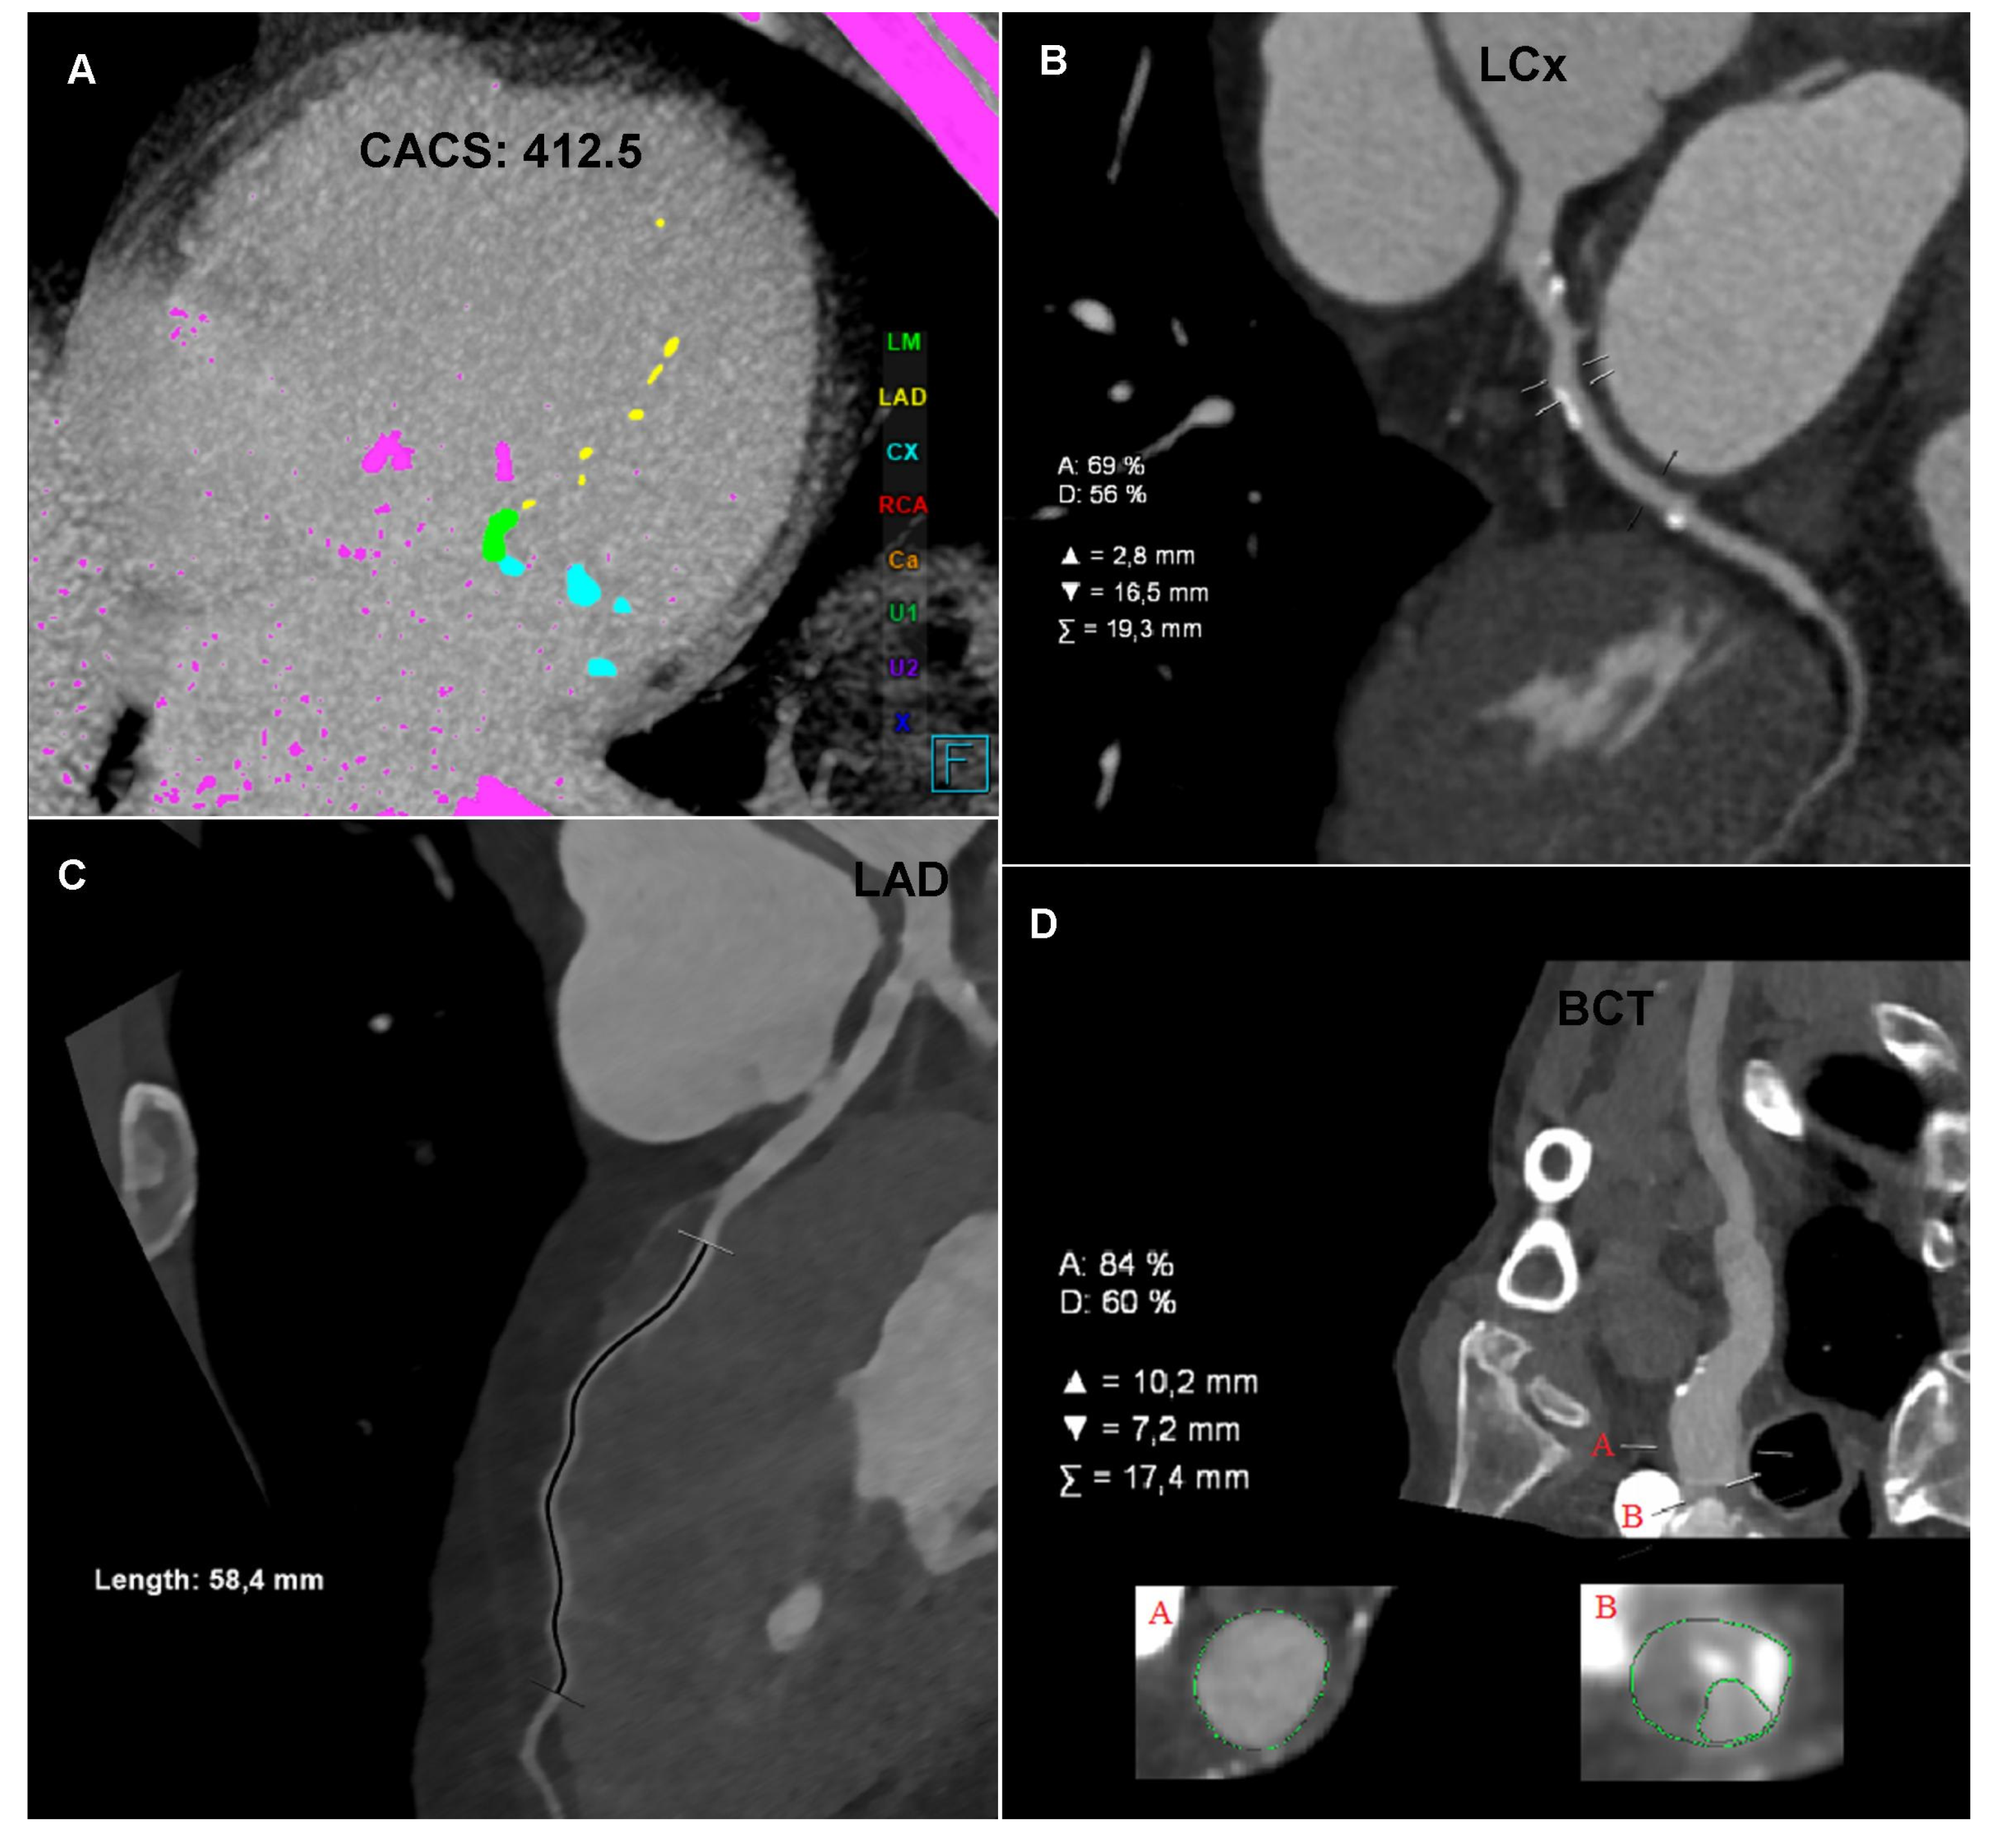

The CTA of the coronary arteries, performed using a 384-slice Siemens Force CT, revealed a coronary artery calcium score of 412.5 (left main (LM): 185, left anterior descending (LAD): 16.7, and left circumflex (LCx): 210.8), the value of which indicated a high risk of a significant coronary artery disease (Figure 1A); the examination revealed numerous atherosclerotic plaques of various morphotic types in the coronary arteries, causing short-segment stenosis, up to 50–70% within the left circumflex, right behind the origin of the 1. marginal branch (Figure 1B) and the long muscular bridge within the middle section of the left anterior descending, about 5.8 cm long (Figure 1C). The CTA images of the coronary arteries corresponded to level three in the CAD-RADS classification, meaning a moderate coronary disease with the presence of moderate LCx stenosis requiring an objective evaluation, optimally via functional tests [1].

Figure 1.

Computed tomography angiography (CTA): (A) Coronary CTA. Native phase. Axial reconstruction. Coronary artery calcium score measurement. The colors indicate the calcifications assigned to specific coronary arteries. (B) Coronary CTA. Angiographic phase. Curved multiplanar reconstruction (cMPR). Left circumflex (LCx). Measurement of the degree of stenosis. (C) Coronary CTA. Angiographic phase. Curved multiplanar reconstruction (cMPR). Left anterior descending (LAD). Measurement of the length of the myocardial muscle bridge. (D) Carotid CTA. Angiographic phase. Curved multiplanar reconstruction (cMPR). Brachiocephalic trunk (BCT). Measurement of the degree of ostial stenosis. The letter A indicates the level of vessel lumen measurement at the reference level, the letter B indicates the level of vessel lumen measurement at the level of maximum stenosis. Computed tomography angiography (CTA): (E) Carotid CTA. Angiographic phase. Volume rendering technique reconstruction (VRT). Arrows mark the recessive right vertebral artery (RVA) and the dominant left vertebral artery (LVA). (F) Carotid CTA. Angiographic phase. Curved multiplanar reconstruction (cMPR). Left subclavian artery (LSA). Measurement of the degree of stenosis. (G) Carotid CTA. Angiographic phase. Axial reconstruction. Measurement of the density of the proximal sections of the internal carotid arteries. Lower density of contrasted blood in the right carotid arteries. (H) Carotid CTA. Angiographic phase. Axial reconstruction. Measurement of the density of the cerebral arteries. Lower density of contrasted blood in the right cerebral arteries.

The CTA of the carotid and vertebral arteries performed using a 384-slice Siemens Force CT revealed a typical origin system of the aortic arch branch, numerous atherosclerotic plaques of various morphotic types in the aortic arch and its branches, significant ostial stenosis of the brachiocephalic trunk by 70–90% of the vessel lumen (Figure 1D), recessive right vertebral artery (Figure 1E), and ostial insignificant stenosis of the left subclavian artery (Figure 1F). In the CTA the right carotid arteries and the right cerebral arteries were characterized by a significantly lower lumen density compared to the contralateral side (Figure 1G,H), which may indicate impaired flow or its direction reversal. The CTA image of the carotid and vertebral arteries corresponded to significant stenosis of the brachiocephalic trunk with symptoms of the steal syndrome.